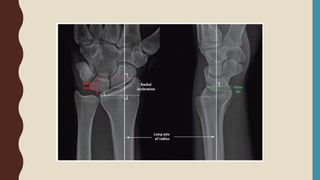

• 3 view of the wrist including true PA(PA zero), Lateral +/- Oblique

• Oblique view – useful for assess radial comminution, depression of radial styloid

15

26

RADIOGRAPHIC FINDINGD

• Extra or intra-articular fracture

• Dorsal angulation

• Dorsal tilt

• Dorsal comminution

• Radial shortening

• Ulnar styloid fracture

• ( Ulnar variance )